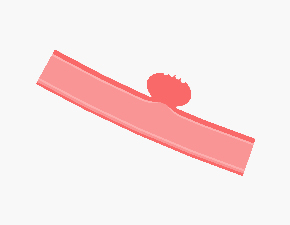

4. 동맥류 경부 결찰수술

- 결찰술은 머리의 피부와 뼈를 절개한 후 동맥류를 찾아 들어가 동맥류의 목을 클립 같은 기구로 영구히 없애버리는 치료방법으로, 오랫동안 이어져 온 대표적인 치료 방법입니다.